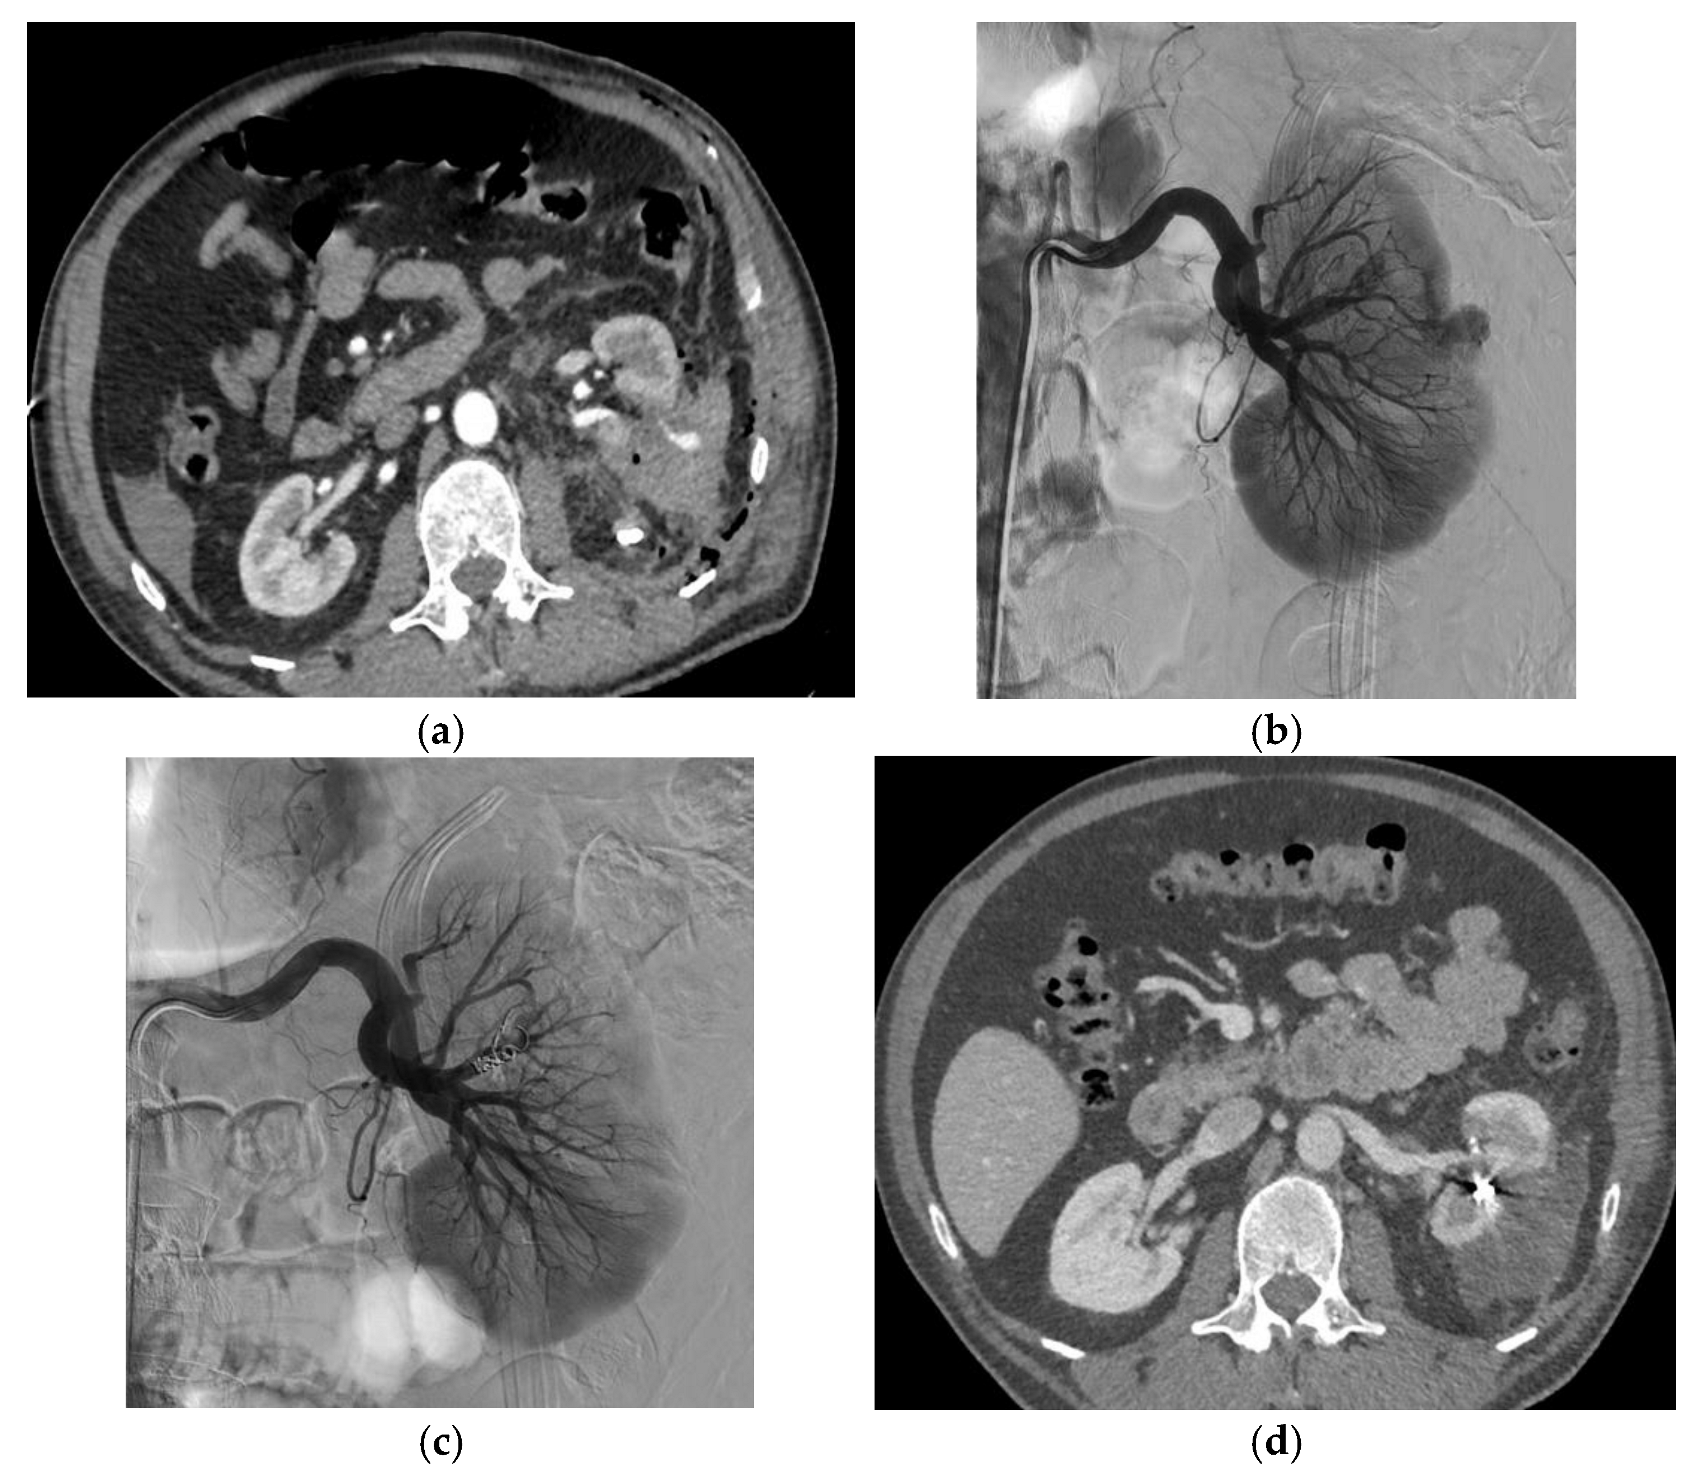

3.2. Endovascular Treatment

| Iatrogenic vascular lesion | |

| Number of renal false arterial aneurysms | 47 |

| Number of renal arteriovenous fistulas | 9 |

| Number of patients with both | 7 (28%) |

| Aneurysm size (mm) | 10.5 (±4.7) |

| Diagnostic imaging | |

| Computed tomography a | 22 (88%) |

| Angiography | 3 (12%) |

| Embolization technique | |

| Coils | 8 (32%) |

| Liquid embolic agent | 8 (6 Glubran2, 1 Onyx, 1 Gelatispon) (32%) |

| Coils and liquid embolic agent | 9 (36%) |

| Technical success at first attempt | 24 (96%) |

| Technical success at first or second attempt | 25 (100%) |

| Clinical success, one attempt | 24 (96%) |

| Clinical success, one or two attempts | 25 (100%) |